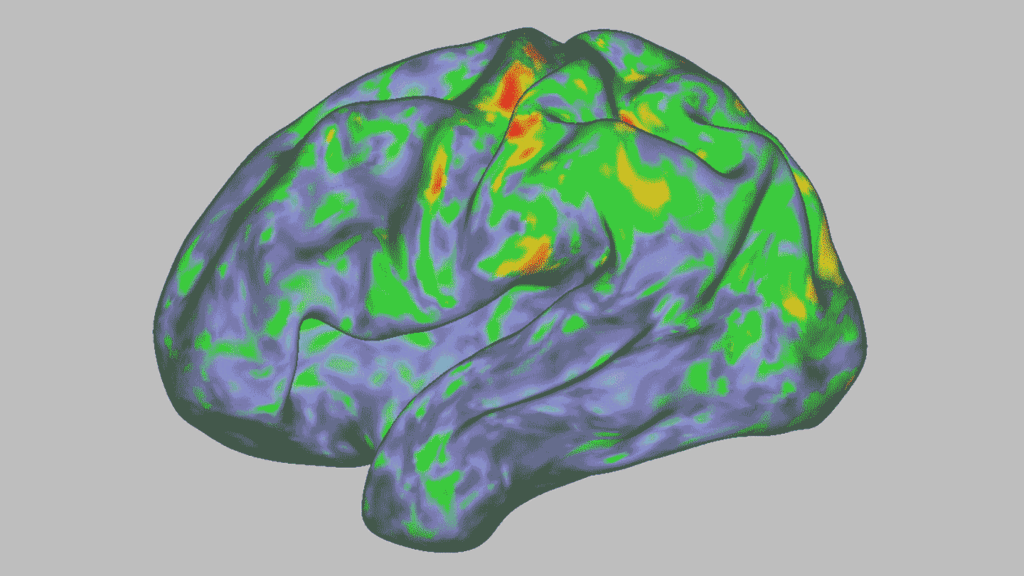

Signs of those experiences showed up in the MRI scans. The team saw that psilocybin seemed to wipe clean the participants’ neural fingerprints. Dosenbach has an analogy to explain the brain changes in the scans: “You’d be like, ‘That is my face, and that is your face.’ And then you took a medicine, and we both had a puppy face — very similar, but very different from our normal faces.”

Some of the biggest changes were in a brain system known as the default mode network, or DMN. This coordinated group of brain regions is active when nothing particular is happening. Scientists think that the DMN has a role in creating our sense of self (SN: 7/3/09). “It’s multiple parts of the brain across both hemispheres, but they’re all activating and deactivating in a very organized, synchronous way,” Siegel says. “And with psilocybin, it essentially becomes chaos.”

The findings add to earlier work that sought to understand how psychedelic drugs change brains and show that the effects are far from simple. “Psilocybin is not simply tuning brain activity up or down,” Kwan says. “The results paint a more complex and nuanced picture for how psychedelics change neural activity dynamics than previously thought.”